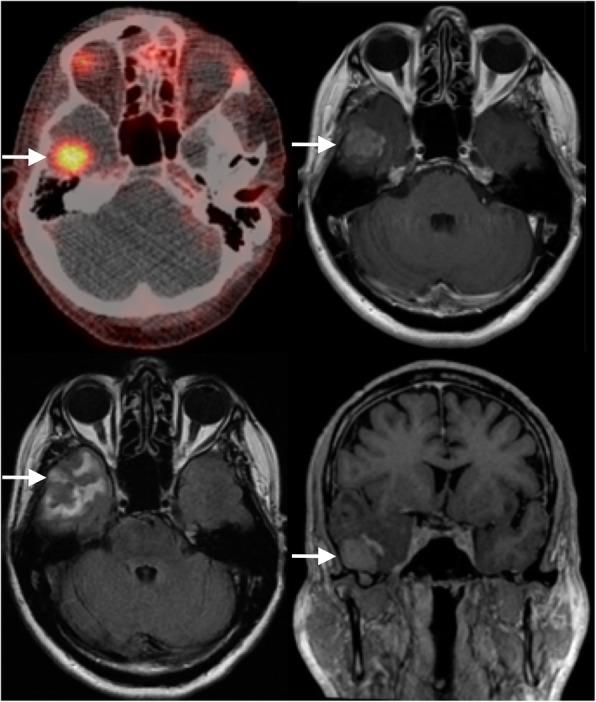

Brain metastases from prostate cancer are rare and usually only occur in the context of widespread systemic disease. This is the first case report of a solitary brain oligometastasis, in a neurologically intact prostate cancer patient with no other systemic disease, detected using [Ga]Ga-THP-PSMA PET/CT and only the second one using a PSMA-based radiopharmaceutical.

We report the case of a prostate cancer patient presenting 5 years after robot-assisted laparoscopic prostatectomy with biochemical recurrence, no neurological symptoms, and in the absence of metastatic lesions in the body on conventional imaging. A solitary cerebral metastasis was detected using [Ga]Ga-THP-PSMA PET/CT, surgically resected, leading to a drop in serum PSA and a good recovery.

In this case, [Ga]Ga-THP-PSMA PET/CT resulted in a major change in clinical management and avoided additional morbidity associated with delayed diagnosis and treatment. This report demonstrates the importance of considering the presence of metastatic disease outside the conventional locations of prostate cancer spread, as well as the importance of ensuring comprehensive [Ga]Ga-PSMA PET/CT coverage from vertex to upper thighs.